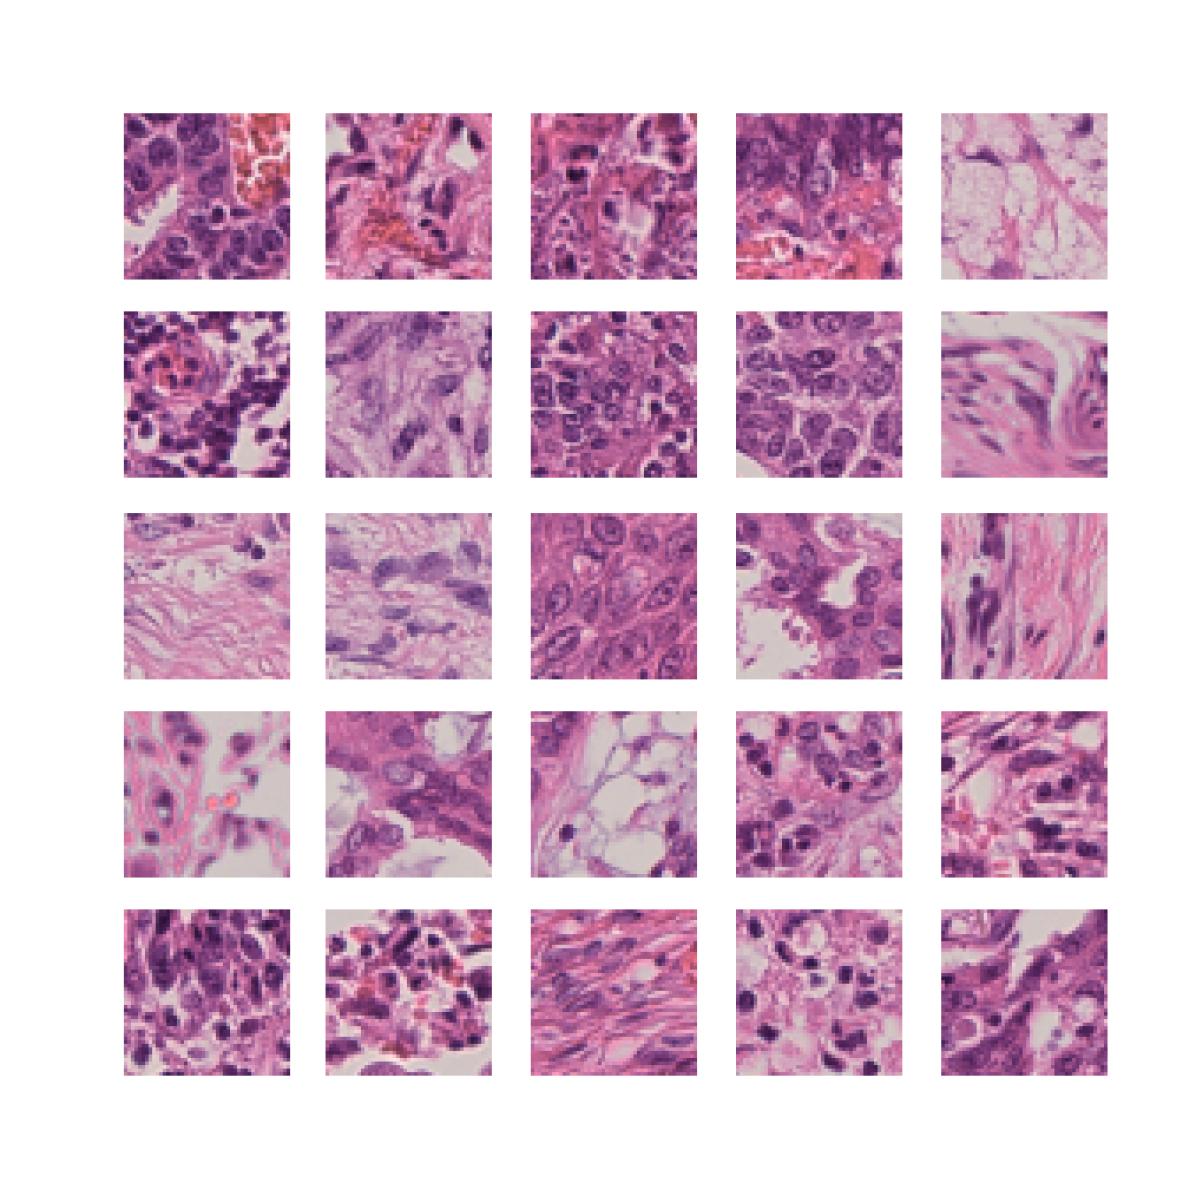

We first demonstrate that TriDeNT ♆ is highly effective for improving the quality of representations in the primary encoder by distilling privileged information from immunofluorescence (IF) images to H&E stained images (Figure 2 and Table S6). Models are trained on the SegPath dataset [22], which consists of eight subsets of H&E images paired with an image derived from the IF stain of a consecutive slice for one of eight antibodies. Evaluation is performed on four standard computational pathology tasks (see Section S2 for full details). We find that the model significantly increases performance by up to 101% compared to a privileged baseline model. TriDeNT ♆ retains not only the useful features shared between inputs, but also the features which are only present in the primary data, leading to better performance on all evaluated tasks. Even in cases where the privileged data does not appear to significantly improve performance, such as staining with CD235a, TriDeNT ♆ still achieves comparable performance, as it obtains a strong supervisory signal from the additional H&E branch. This is in contrast with the privileged Siamese setting, where it is clear that the pairing can cause a seismic drop in classification accuracy if the privileged data is not informative for the task being evaluated.

2.2 Embedding Knowledge from Additional Brightfield Images

To demonstrate the generality of the method, we train models on the BCI dataset [4] of paired H&E and brightfield IHC patches. We only perform evaluation on the BCI, NCT and PanNuke datasets, as the BCI dataset is a breast cancer dataset, while the Singapore and MHIST datasets are prostate and colorectal polyp specimens respectively, which are far out of the training distribution. We include the NCT dataset, despite comprising only colorectal tissue, as these patches are well curated into different tissue type classes which mostly bear a strong resemblance to those in breast cancer samples. Strikingly, TriDeNT ♆ outperforms the supervised baseline by a large margin on the BCI task. We propose that there may be features weakly present in H&E stains which are highly predictive of HER2 status, and the pairing with IHC stains which contain those features very strongly results in this improved performance.

As Table 1 shows, we find that TriDeNT ♆ is also highly effective on all tasks compared to the unprivileged Siamese baseline. As there is more information in the privileged paired data, the privileged baseline is considerably higher for this task. Despite this, TriDeNT ♆ still outperforms both comparable baselines on all tasks but one, achieving improvements of up to 25.1% compared to the unprivileged baseline and up to 5.8% compared to the privileged baseline. There is only a single task where TriDeNT ♆ does not improve performance: evaluation on the PanNuke dataset of a model trained with the VICReg loss, performing 1.6% less than the privileged baseline. The brightfield IHC stains contain considerably more task-relevant information for cell segmentation, so this is unsurprising. This effect can be understood visually as the IHC ‘weak’ quadrant in Figure 1(a) being very narrow and containing very few features. Most task-relevant features are strongly present in the IHC and therefore there is less to be gained by adding the few missing weak features.

2.3 Image Annotations are an Effective Source of Privileged Information

We find that TriDeNT ♆ is effective not only for integrating additional sources of data, but also for manually determining the most useful aspects of the data which should be learned, where the user has some prior knowledge to incorporate into the dataset. This is intuitively the opposite of traditional machine learning approaches, where the user has to handcraft inputs to be passed to the model, and the model only learns from those features. With our approach, the user can manually handcraft inputs, such as the segmentation masks in this example, while still giving the model the flexibility to learn other features not known a priori to the user. The results in Table 2 demonstrate that TriDeNT ♆ is able to train encoders which retain the features of both the nuclei and the background/connective tissue. We see performance improvements of up to 42.4% compared to the privileged baseline, and up to 5.2% compared to the unprivileged baseline.

These results also suggest that, in the privileged Siamese case, the features that are learned are those relating to the shape of the nuclei, rather than any sub-nuclear features or features relating to the connective tissue which would enable better identification of tissue and cell types.

To further analyse the learned representations, we produce UMAP projections of the latent space labelled with the tissue types for the NCT tissue type classification task, as shown for CD3CD20 and SMA in Figure 4(a), and for all SegPath stains in Figures S8 and S9. These figures make the reasons for the varying performance of the privileged Siamese model more apparent. For stains with better performing privileged Siamese models, such as SMA, the UMAPs are very similar between Siamese methods and TriDeNT, with well-differentiated tissue type clusters. In those with worse performance, such as ERG, the tissue types are poorly differentiated, often with only adipose and background forming distinct clusters from the other classes. On closer inspection, it is notable in these projections that TriDeNT ♆ produces more well-defined and separated clusters in general than Siamese networks. This is further evidenced in Figure S7, where TriDeNT ♆ is shown to identify clusters with overexpression of a given gene significantly more effectively than an unprivileged Siamese model.

We also analyse the activation maps for each model using GradCAM as described in section S3. This offers more insight into the areas of the image which are contributing most heavily to the models’ representations. In Figure 4(b) we present some representative examples, however, a larger selection which was chosen at random is presented in Figures S10 to S25. The larger selection makes it easier to see the emergent patterns, including that privileged Siamese models tend to mainly identify features which are strongly present in both inputs, while unprivileged Siamese models tend to learn more diffuse features that are not specific to one cell phenotype or image region. TriDeNT ♆ incorporates both sets of features, learning both features specific to the privileged data and more the general features associated with unprivileged Siamese networks.